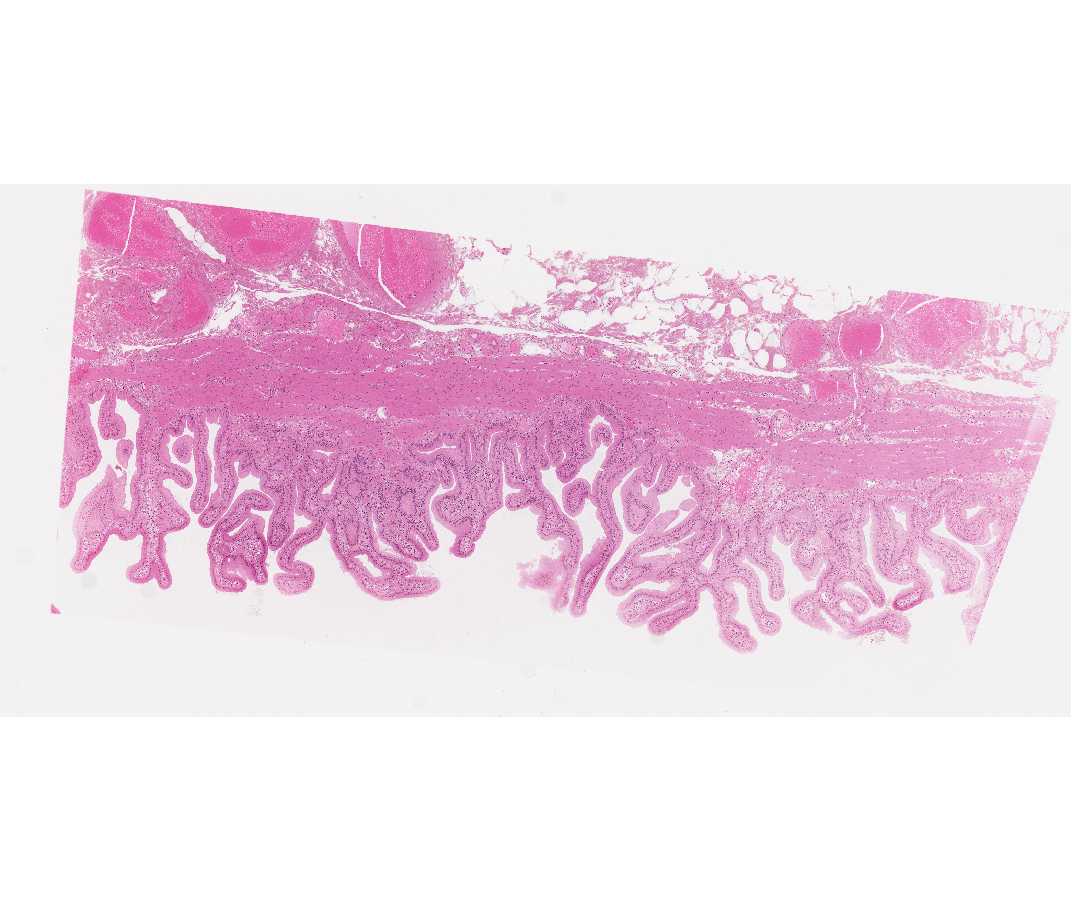

#115 Gall Bladder, Hematoxylin & Eosin (H&E)

This is a portion of the gall bladder that has been stained with hematoxylin (blue) and eosin (red). Beginning with low magnification identify the nuclei of cells (blue) and their cytoplasm (light red). Go to higher magnifications to see these in more detail.